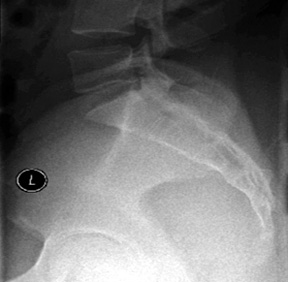

It is important that the pelvis is properly positioned so the sacrum and sacroiliac joints are symmetrically displayed. When accurately positioned, the PA sacrum view will demonstrate the median sacral crest aligned with the symphysis pubis and the ischial spines equally demonstrated in relationship to the pelvic brim. The patient stands facing the bucky as close as possible. Check feet and torso for rotation. Measure thickness at the level of the trochanters. Tube angle is 15° caudal to reduce foreshortening of the sacrum. Locate the PSIS and place the horizontal CR (central ray) 1-2 inches below the PSIS or mid-sacrum. The vertical CR is the mid-sagittal plane. (Figure 1)

Figure 2: PA view of the sacrum.

Collimation is slightly less than the film size (8 x 10 portrait). A properly positioned PA sacrum view will demonstrate the entire fifth lumbar vertebra, symphysis pubis, and both sacroiliac joints. (Figure 2)